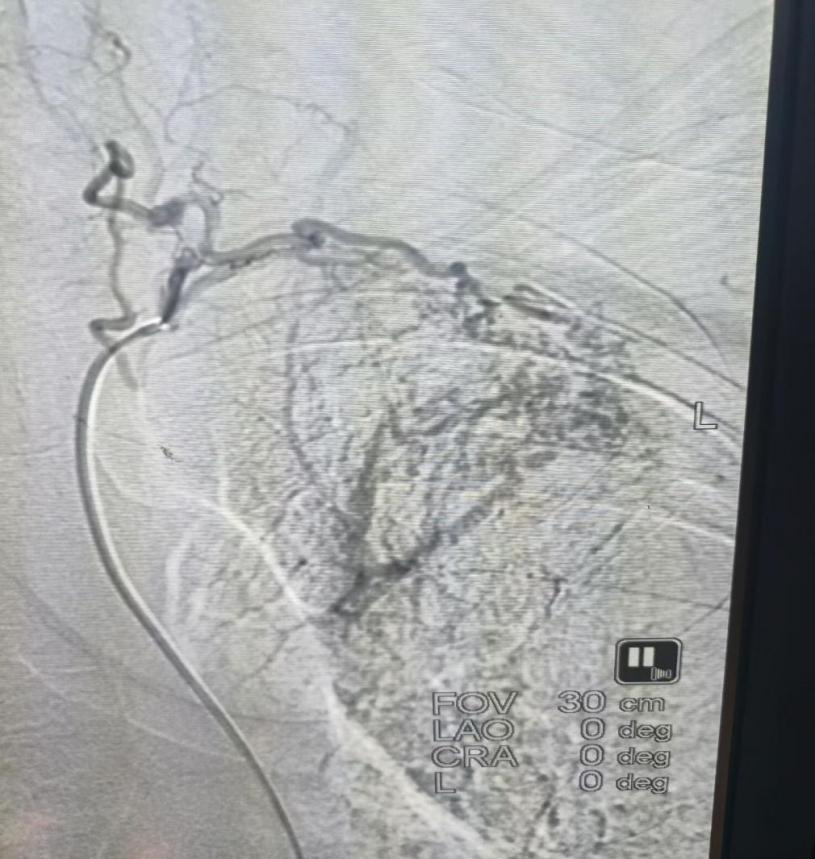

患者谭某因反复咯血入院,每次咯血量约200—300毫升。经询问,患者既往无支气管扩张等相关病史。为明确出血原因,在科主任、副主任医师肖朝辉的带领下,介入团队对患者病情进行全面评估,并在局部麻醉下实施血管造影检查。

术中发现,患者左肺上叶的异常供血来源于一条罕见责任血管——“甲颈干”,且伴有动静脉瘘形成,终于找到导致他反复咯血的直接原因。面对这一少见的解剖变异,介入团队沉着应对、精准定位,成功对左侧胸廓内动脉及相关支气管动脉远端实施栓塞治疗。